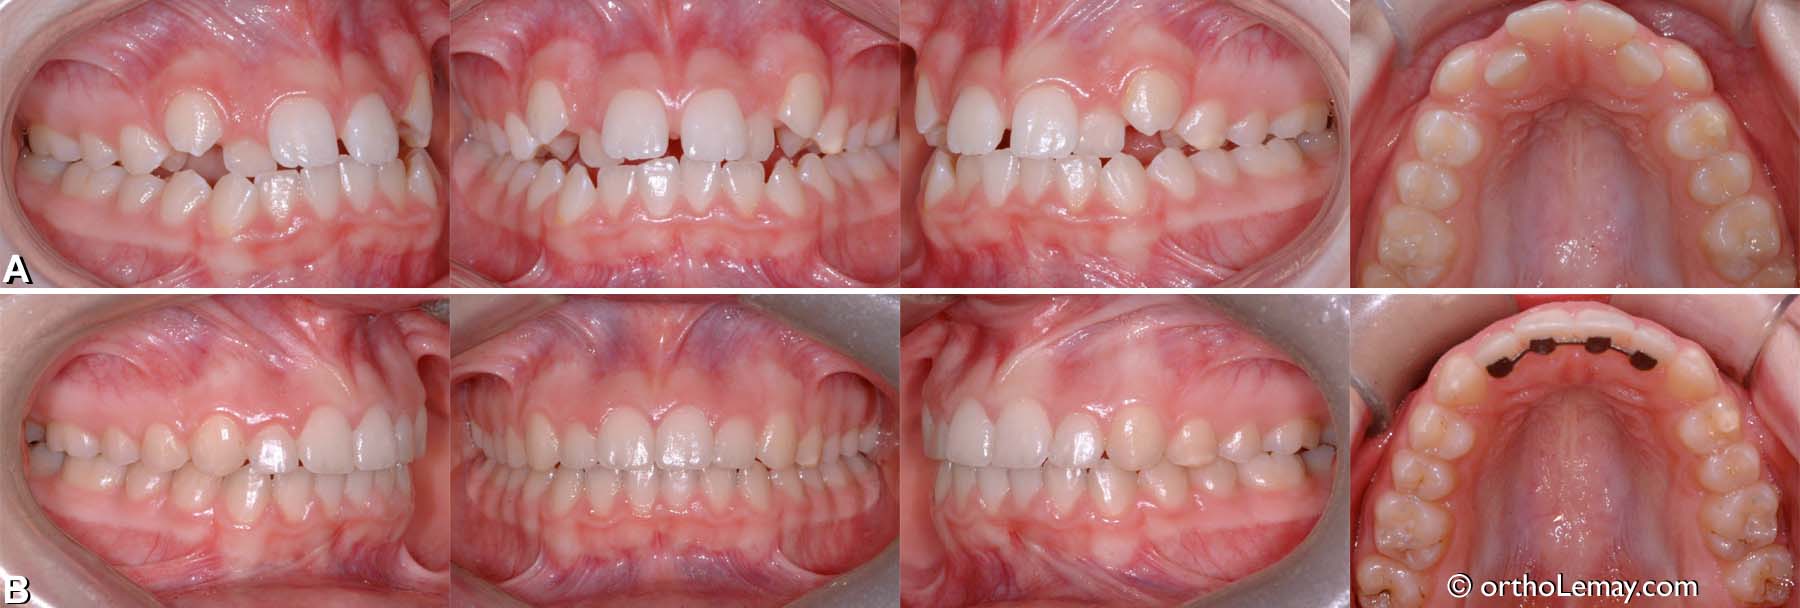

Expansion dento-alvéolaire faite aux deux arcades et ayant permis de corriger le chevauchement dentaire et manque d’espace chez une femme de 22 ans.

• (A) Avant le traitement.

• (B) après les corrections orthodontiques.

• Note: les troisièmes molaires supérieures ont été extraites car elles n’étaient pas fonctionnelles.